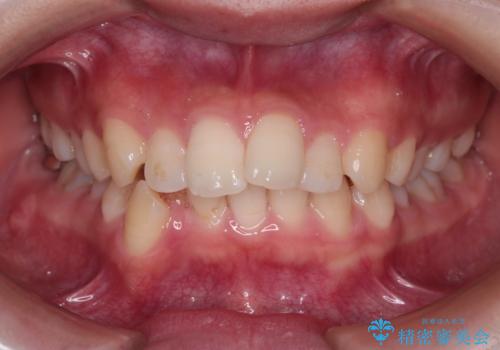

- 前歯から奥歯にかけて歯の重なりが激しい歯のがたつき(重度叢生)を主訴にご来院されました。精密検査の結果、歯が並ぶスペースが大幅に不足しており、歯並びを整え、口元を美しく引っ込めるためには、スペースの確保が必要と診断しました。そこで、上下左右の第一小臼歯(4番目の歯)を計4本抜歯し、そのスペースを利用して歯並び全体を整える抜歯矯正の治療計画を立案。装置には、透明で目立たないインビザラインを採用し、審美性と治療効果の両立を目指しました。

今回の治療では、重度の叢生を改善するため、まず計画通り上下左右4本の小臼歯を抜歯し、歯を並べるための十分なスペースを確保しました。装置には透明で取り外し可能なインビザラインを使用。抜歯によってできたスペースを最大限に活用し、マウスピースを定期的に交換しながら、デコボコを解消しつつ、前歯を効果的に後退させました。

治療の結果、長年の悩みであった重度の歯のがたつきが解消され、口元の突出感も改善。機能的にも安定し、審美的にも美しい、理想的な歯並びを獲得していただけました。